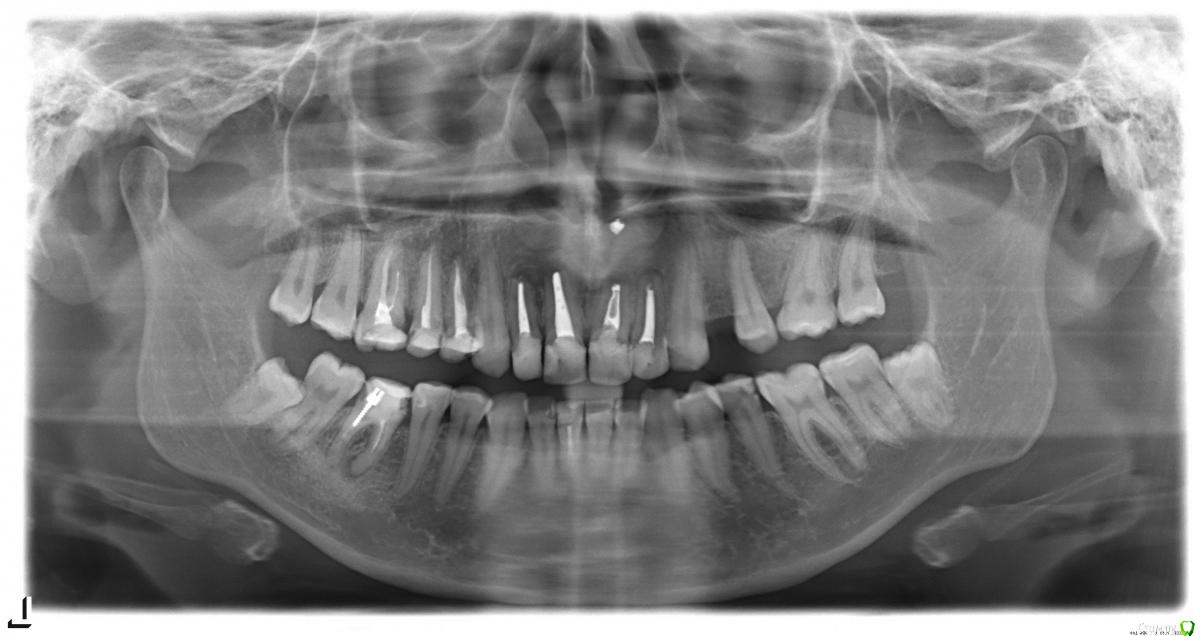

Анна 1986 Опубликовано 2 апреля, 2015 Поделиться Опубликовано 2 апреля, 2015 Добрый день! Прошу Ваших советов...У меня с детства, начиная лет с 10 образовывались кисты над передними верхними зубами.Каждый раз делали резекции, но с интервалом в 2-3 года все повторялось вновь. Последний раз рецидив был в 2012г., кисту удалили, на ее место поместили спец. материал (не знаю какой).Сейчас снова рецидив (узнала по образующимся свищам)Сходила на консультации к нескольким хирургам, и все сходятся во мнении, что делать резекции нет смысла, надо удалять 4 передних зуба.Хочу попросить оценить план лечения:1. Удаление передних 4 зубов, и через несколько дней поставить съемный протез (косметическая пластинка)2. Через 2-3 месяца - костная пластика3. Через 4-6 месяцев - если костная пластика прошлась успешно - имплантация либо мост на 11 верхних зубов. Очень страшно делать все процедуры, особенно из-за частых кист (скорее всего они образовывались из-за не верно вылеченных в свое время каналов), и страх, что не приживется костная ткань и импланты. Ссылка на комментарий

red_butler Опубликовано 2 апреля, 2015 Поделиться Опубликовано 2 апреля, 2015 хорошо бы сделать Кт, если судить только по ОПГ - вижу проблему только с одним резцом Ссылка на комментарий

Bier Опубликовано 2 апреля, 2015 Поделиться Опубликовано 2 апреля, 2015 Скорее всего резекции были сделаны неправильно, на первый взгляд все зубы можно спасти 1 Ссылка на комментарий

johniola Опубликовано 2 апреля, 2015 Поделиться Опубликовано 2 апреля, 2015 Я бы не торопился удалять эти зубы.Если зубы не подвижны,найдити грамотного хирурга,и повторите резекции с ретроградной пломбировкой мта,а потом поставьте хорошие коронки.Ничего Вам не заменит свои передние зубы,не делайте ошибку. 2 Ссылка на комментарий

red_butler Опубликовано 2 апреля, 2015 Поделиться Опубликовано 2 апреля, 2015 Я забыла уточнить важный момент - передние зубы у меня не свои, там штифты, и сами зубы - пломбызубы у вас свои, просто восстановлены пломбами 2 Ссылка на комментарий